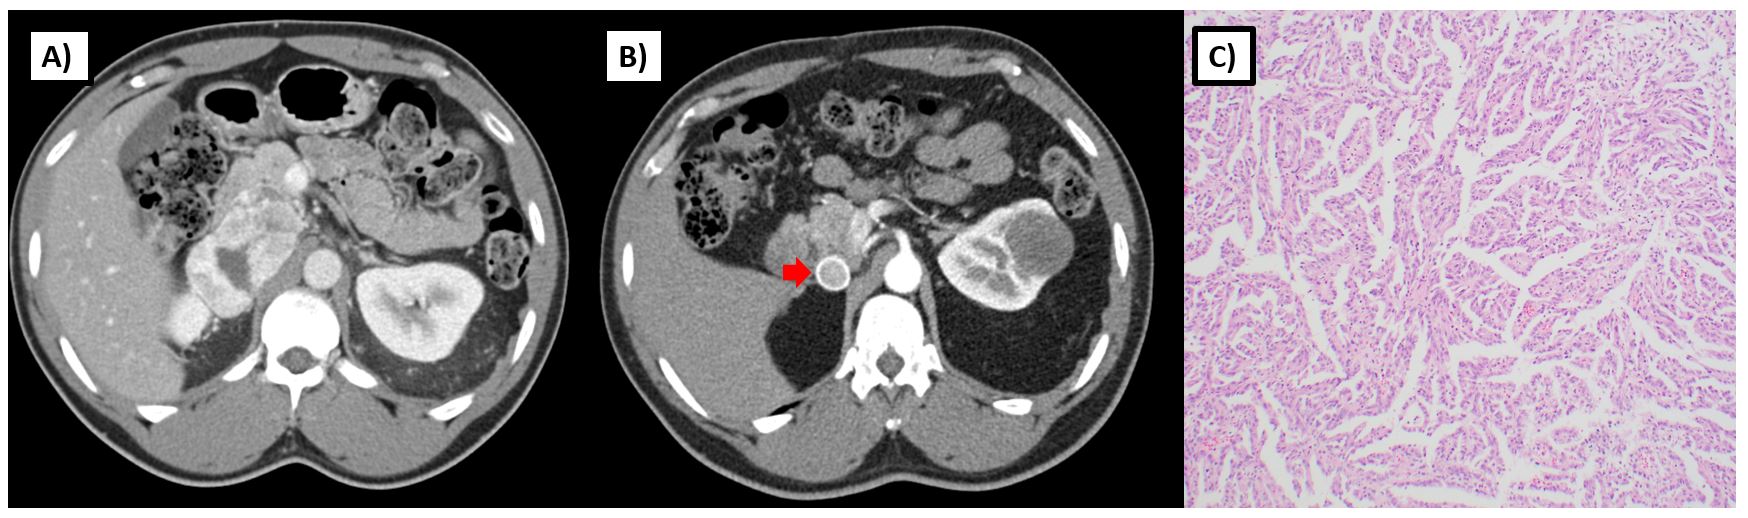

SDH is an enzyme complex that is composed of four subunits (SDHA, SDHB, SDHC, SDHD) and assembled with SDHAF1 and SDHAF2 mitochondrial proteins. This enzyme plays a critical role in mitochondrial respiration; specifically, it catalyzes the oxidation of succinate to fumarate within the Krebs cycle and is also critical to complex 2 of the electron transport chain (Figure 1B). Those with germline loss of function mutations in one of these SDH genes are at risk for paragangliomas, pheochromocytomas, gastrointestinal stromal tumors (GIST), and RCC.28 RCC has been reported in individuals with SDHB, SDHC, and SDHD mutations, and more recently, in patients with SDHA mutations29. Histology can be variable and may depend on the subunit affected. SDHB-deficient tumors are characterized by a unique oncocytic and vacuolated appearance. By contrast, SDHC-deficient tumors tend to present with clear cell histology28,30. Various other histologies, including papillary, sarcomatoid, and unclassified RCCs have been reported in patients with germline mutations of SDH subunit genes (Figure 3).

As opposed to sporadic RCC, SDH-deficient RCC tends to occur at an earlier age with a reported median age of onset 30 years and range from 15 to 61 in one series3. Given that these tumors share common underlying metabolic features with FH-deficient RCC, some may behave in a similarly aggressive manner and present with metastatic disease; however, others may have a more low-grade appearance and present with non-invasive tumors (Figure 3). Although penetrance for paragangliomas and pheochromocytomas are much higher in those with a germline SDH mutation (18-95% by age 60), RCC can also present as the sole finding in such individuals28,31. The true penetrance for RCC in SDH-deficiency is unknown and may vary by the affected subunit, but some reports estimate that risk could be up to 14% by age 7032. Given the variable histologies and uncertain penetrance of RCC in SDH-deficiency, screening recommendations vary. The National Comprehensive Cancer Network recommends abdominal imaging (MRI or CT) with and without contrast every 4-6 years starting at age 1222. However this approach should be individualized based on family risk.